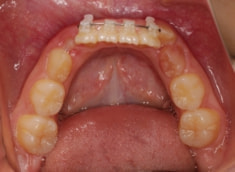

治療開始時

治療開始から11ヶ月